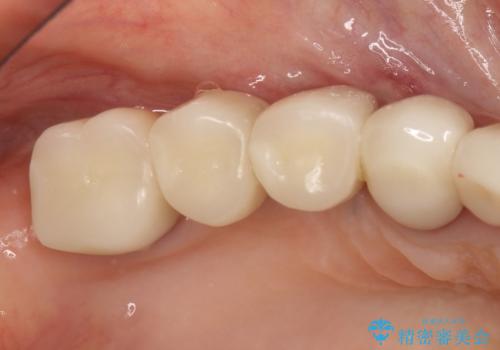

インプラントの種類:Bicon

かぶせ物の種類:PFZ